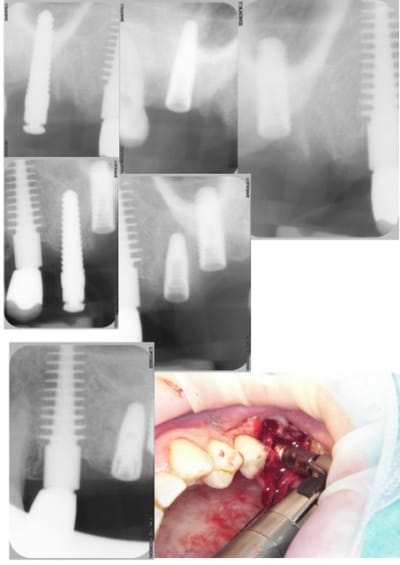

dommage je voulais poser le deuxieme 20mm mais la corticale etait pas d'accord pour laisser passer les osteotomes de Tatum alors adaptation.

les deux implants ne sont pas l'un sur l'autre mais un palatin et l'autre vestibulaire.